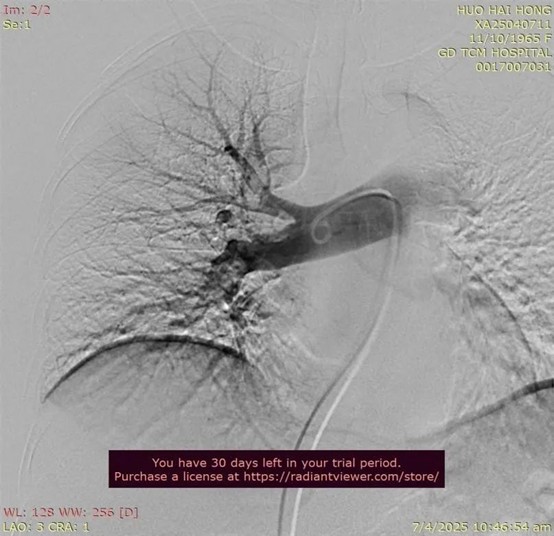

术前造影

② 1%利多卡因局麻,穿刺右侧股静脉,置入6Fr鞘管,穿刺右侧大隐静脉大腿中段,植入5Fr 鞘管,静脉给予3000u肝素;经右侧股静脉鞘管置入泥鳅导丝及造影导管至肺动脉,造影显示右肺动脉主干至右下肺动脉分支多发充盈缺损,左下肺动脉分支可见小范围充盈缺损。